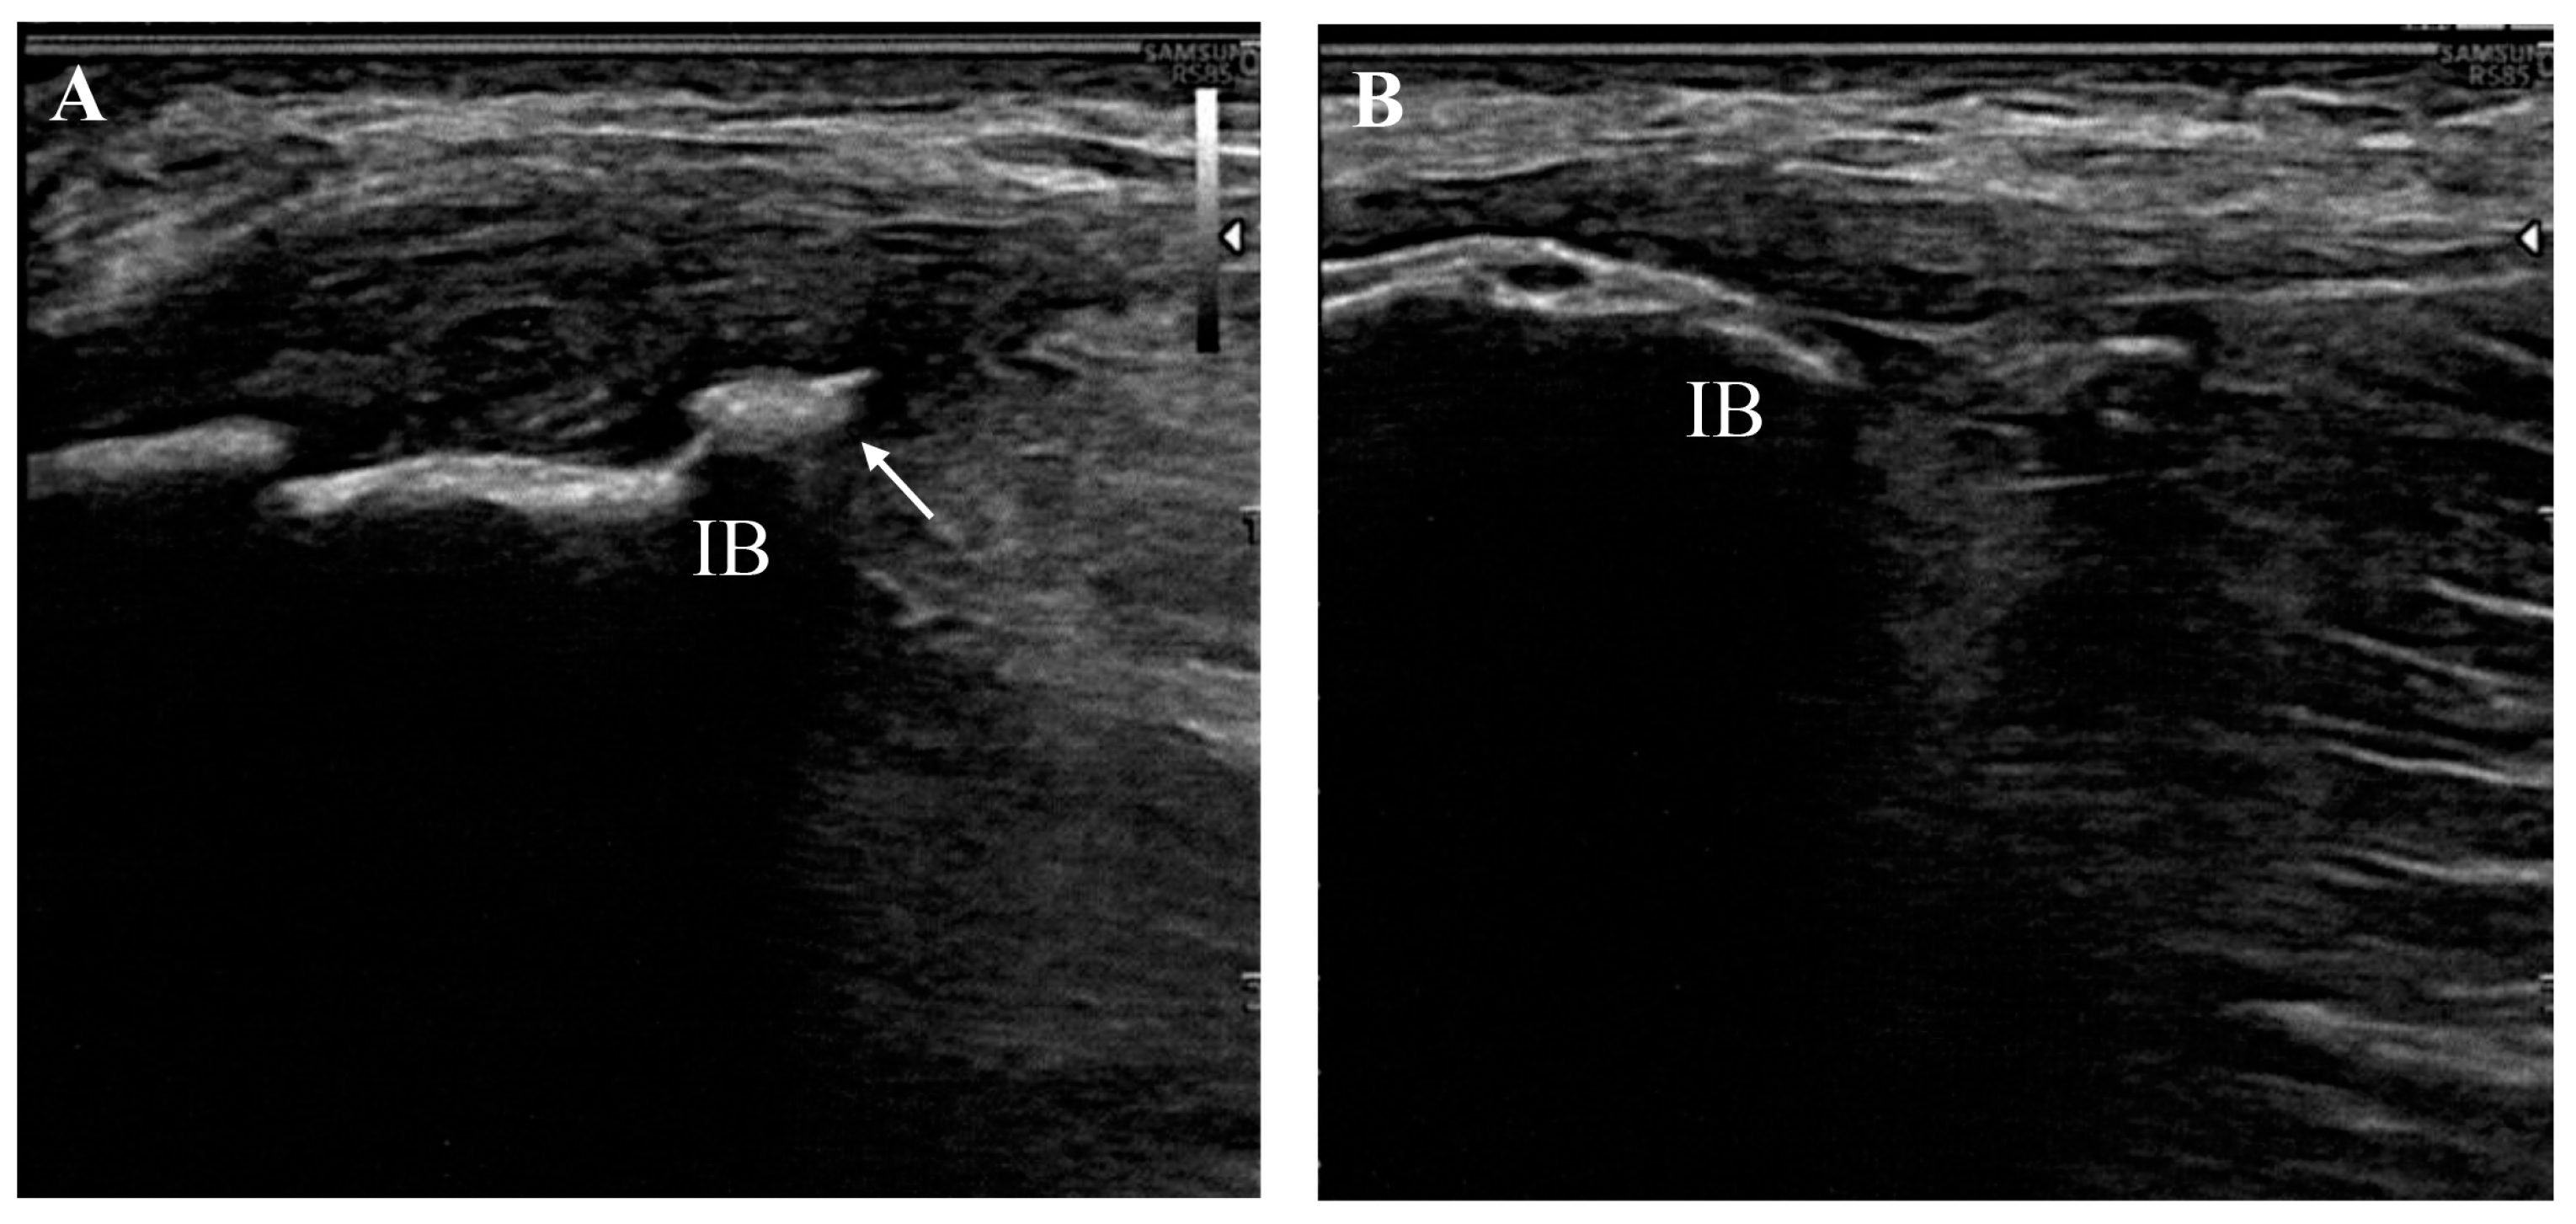

- Manske, R.C.; Wolfe, C.; Page, P.; Voight, M.L.; Bardowski, E. The Utilization of Diagnostic Musculoskeletal Ultrasound in the Evaluation of Gluteus Medius Tendon Pathology: A Perspective for Rehabilitation Providers. Int. J. Sports Phys. Ther. 2024, 19, 642–645. [Google Scholar] [CrossRef] [PubMed]

- Saad, A.; McLoughlin, E.; S Kalia, S.; Almeer, G.; C Azzopardi, C.; Botchu, R. Gluteus Medius Muscle Pathologies—A Case Series & Pictorial Review. J. Orthop. 2020, 21, 270–274. [Google Scholar] [CrossRef] [PubMed]